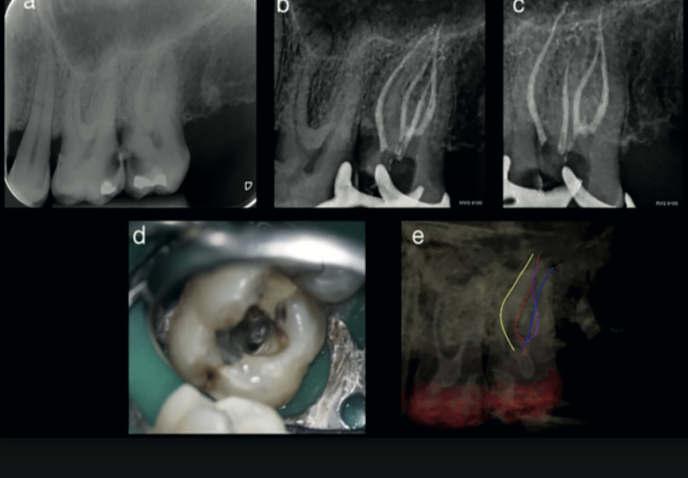

Fig. 4 — Pre-operative, mid-treatment, and operating microscope views showing the two palatal canals alongside the 3D root canal tracing

Fig. 4 (a) Initial periapical radiograph. (b–c) Working length and obturation films. (d) Operating microscope image clearly showing two separate palatal canal orifices. (e) Root canal tracing tool view of the complete canal system.

Endodontic treatment was completed under magnification. Intraoperative findings confirmed exactly what the CBCT had shown: two distinct canals in the palatal root. All canals were instrumented, cleaned, and obturated.

Post-operative radiographs showed satisfactory obturation of all identified canals. At two-year follow-up, the tooth remained asymptomatic with healthy periapical tissues — a successful outcome that would have been unlikely had the second palatal canal been missed.